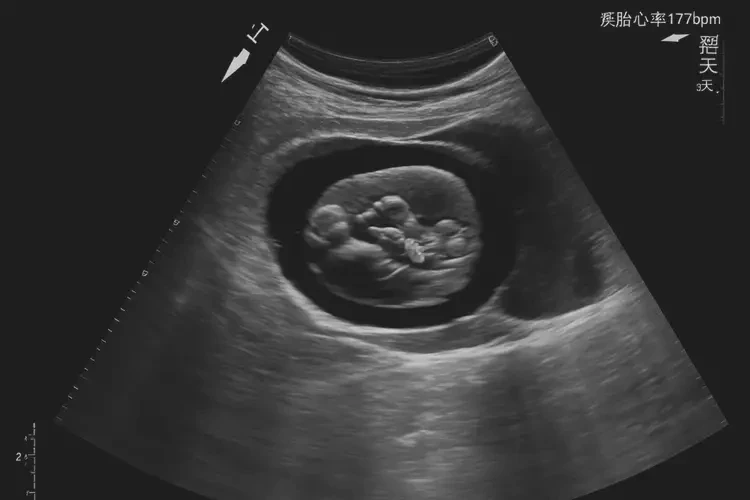

胎心率177次/分钟在孕5周3天的情况下,属于正常范围,胎儿通常可以保住。

在孕早期,胎心率通常较快,正常范围为120-180次/分钟。孕5周3天的胎心率177次/分钟虽然接近上限,但并未超出正常范围。以下是详细分析:

孕5周3天的胎心率177次/分钟属于正常范围,胎儿通常可以保住。但如果出现胎心率异常或其他不适症状,应及时就医,以便医生进行评估和处理。孕妇应保持良好的生活习惯和情绪状态,定期进行产前检查,以确保胎儿的健康发育。